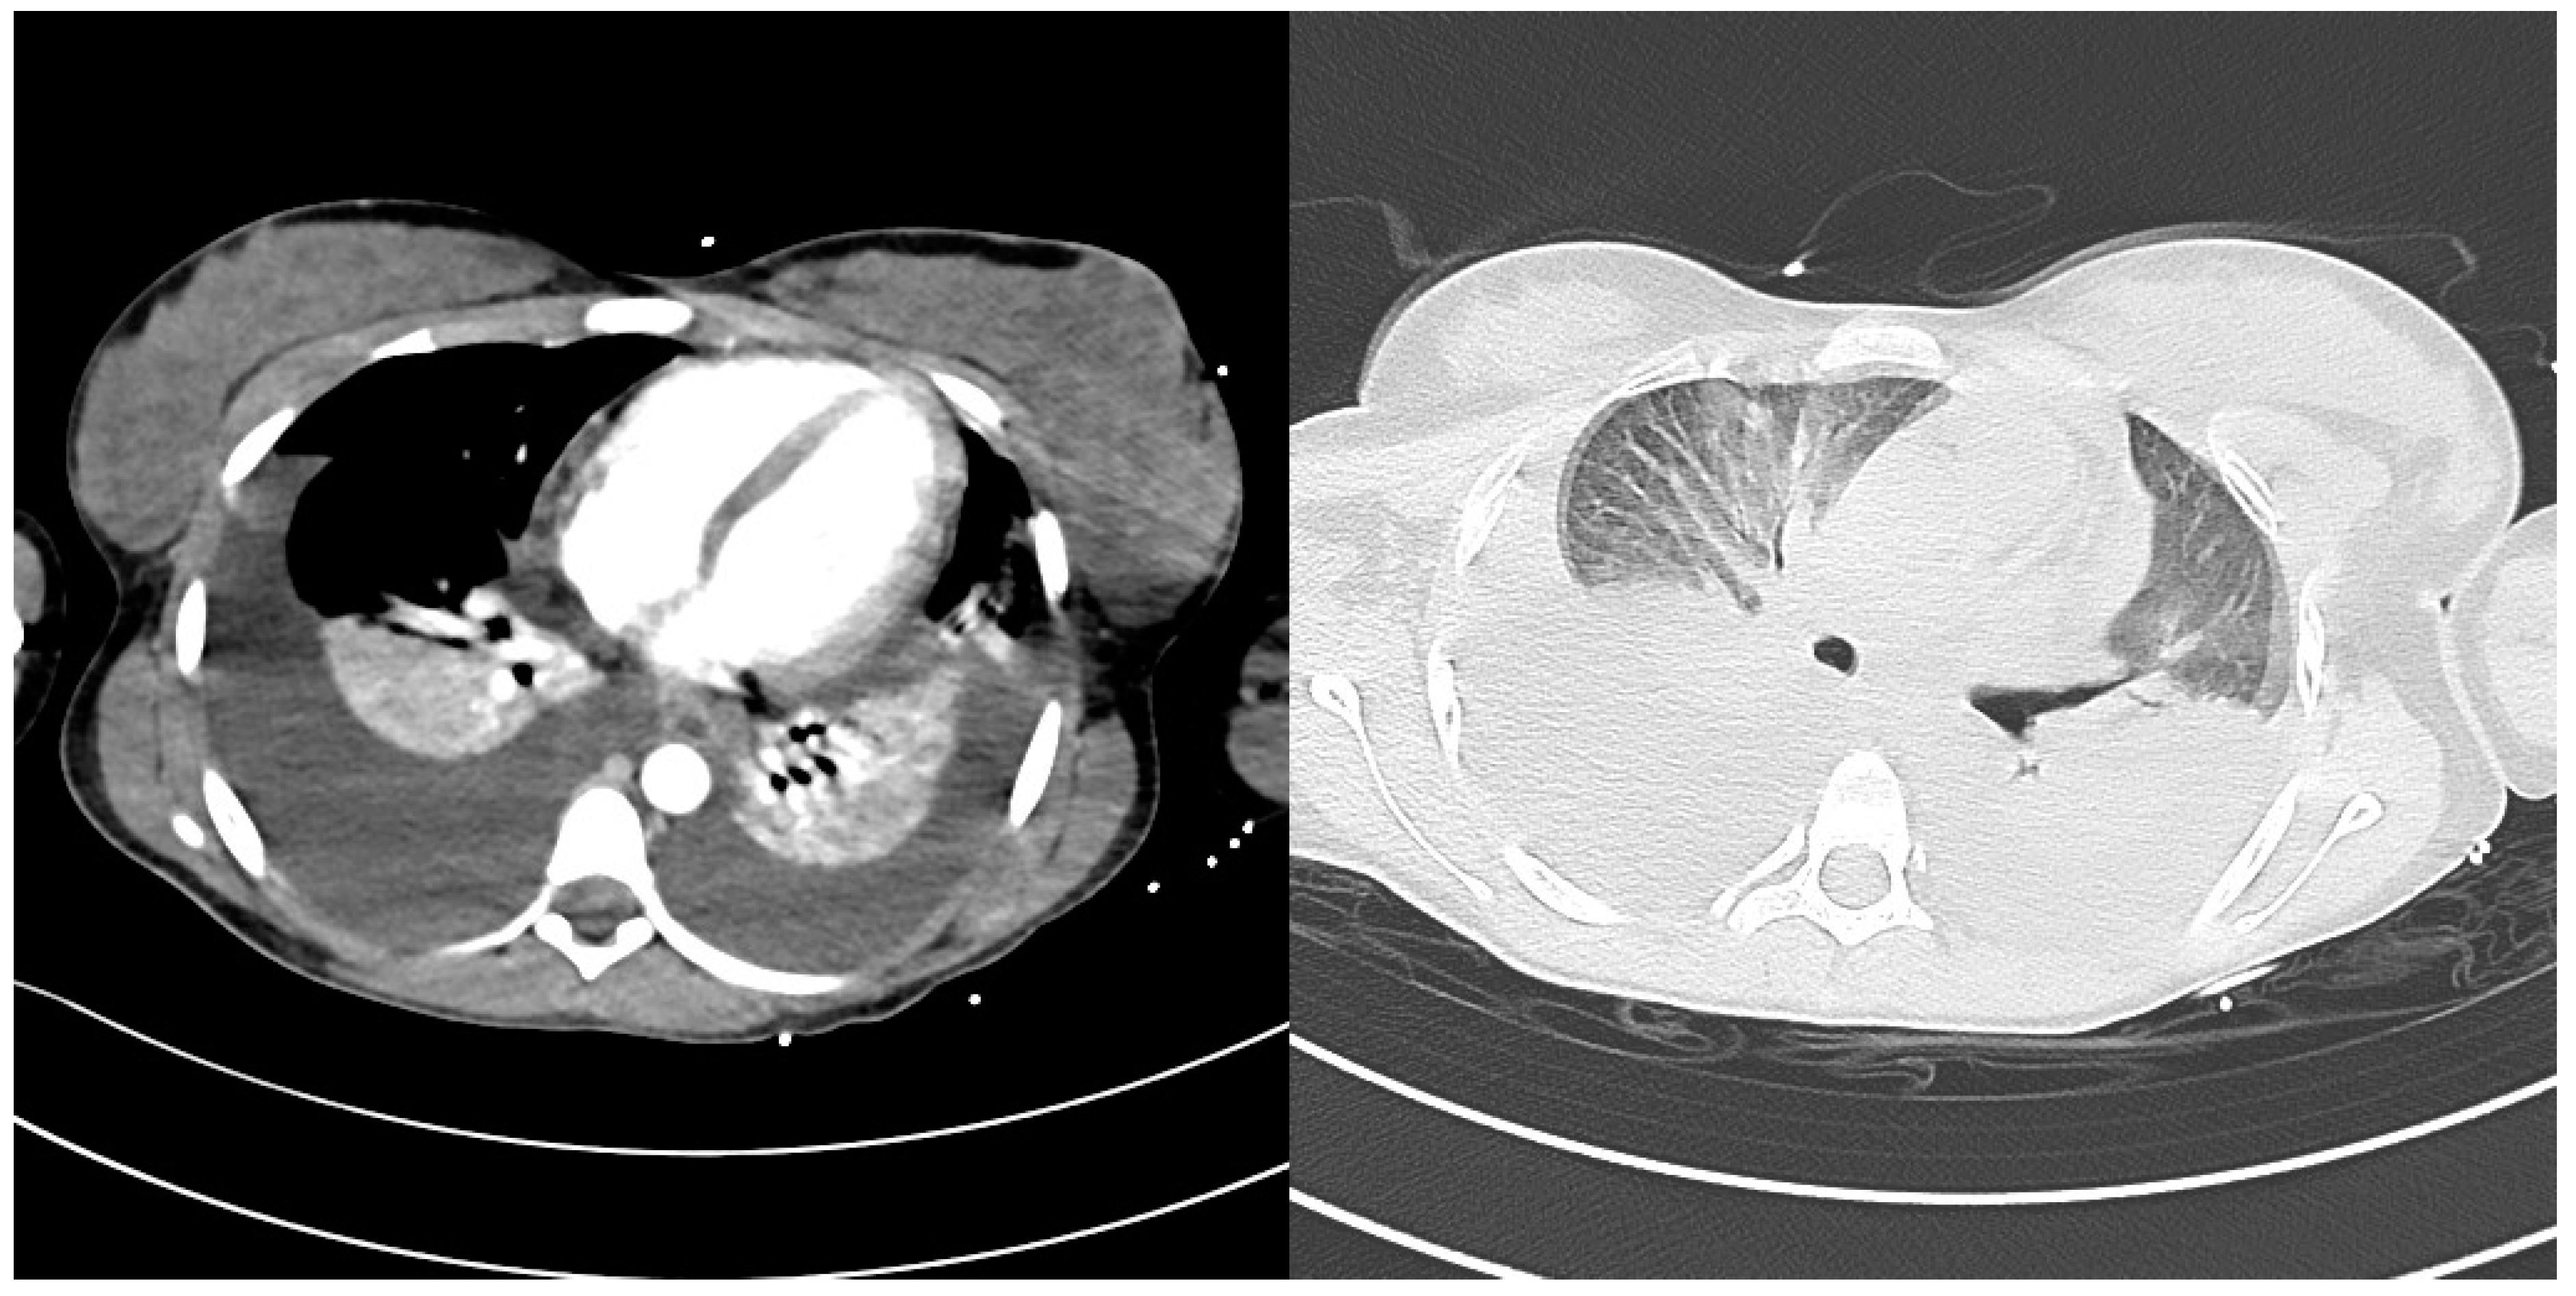

Severe Typhoid Fever Complicated by Superior Mesenteric and Splenic Vein Thrombosis

2. Case Description